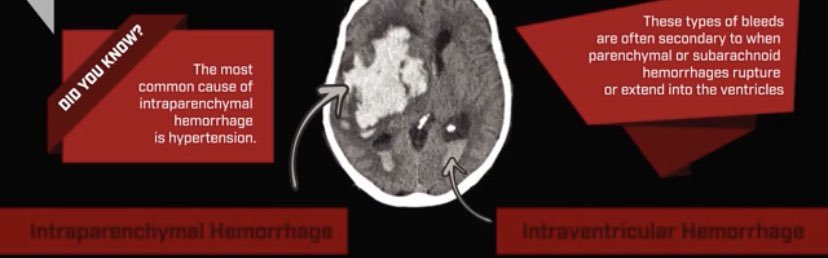

أول حرف وكلمة وأهمّهمْ  Blood

بالذات في حالات الطوارئ

تأكد دايم ان مافيه دم بالأشعة

أنواع hematomas والأشعة لكل نوع

الحرف الرابع "V”

ويقصد فيه ال Ventricle

لازم نستبعد ان مافي دم في الحجرات زي اللي يصير في حالات

Interventricular hemorrhage